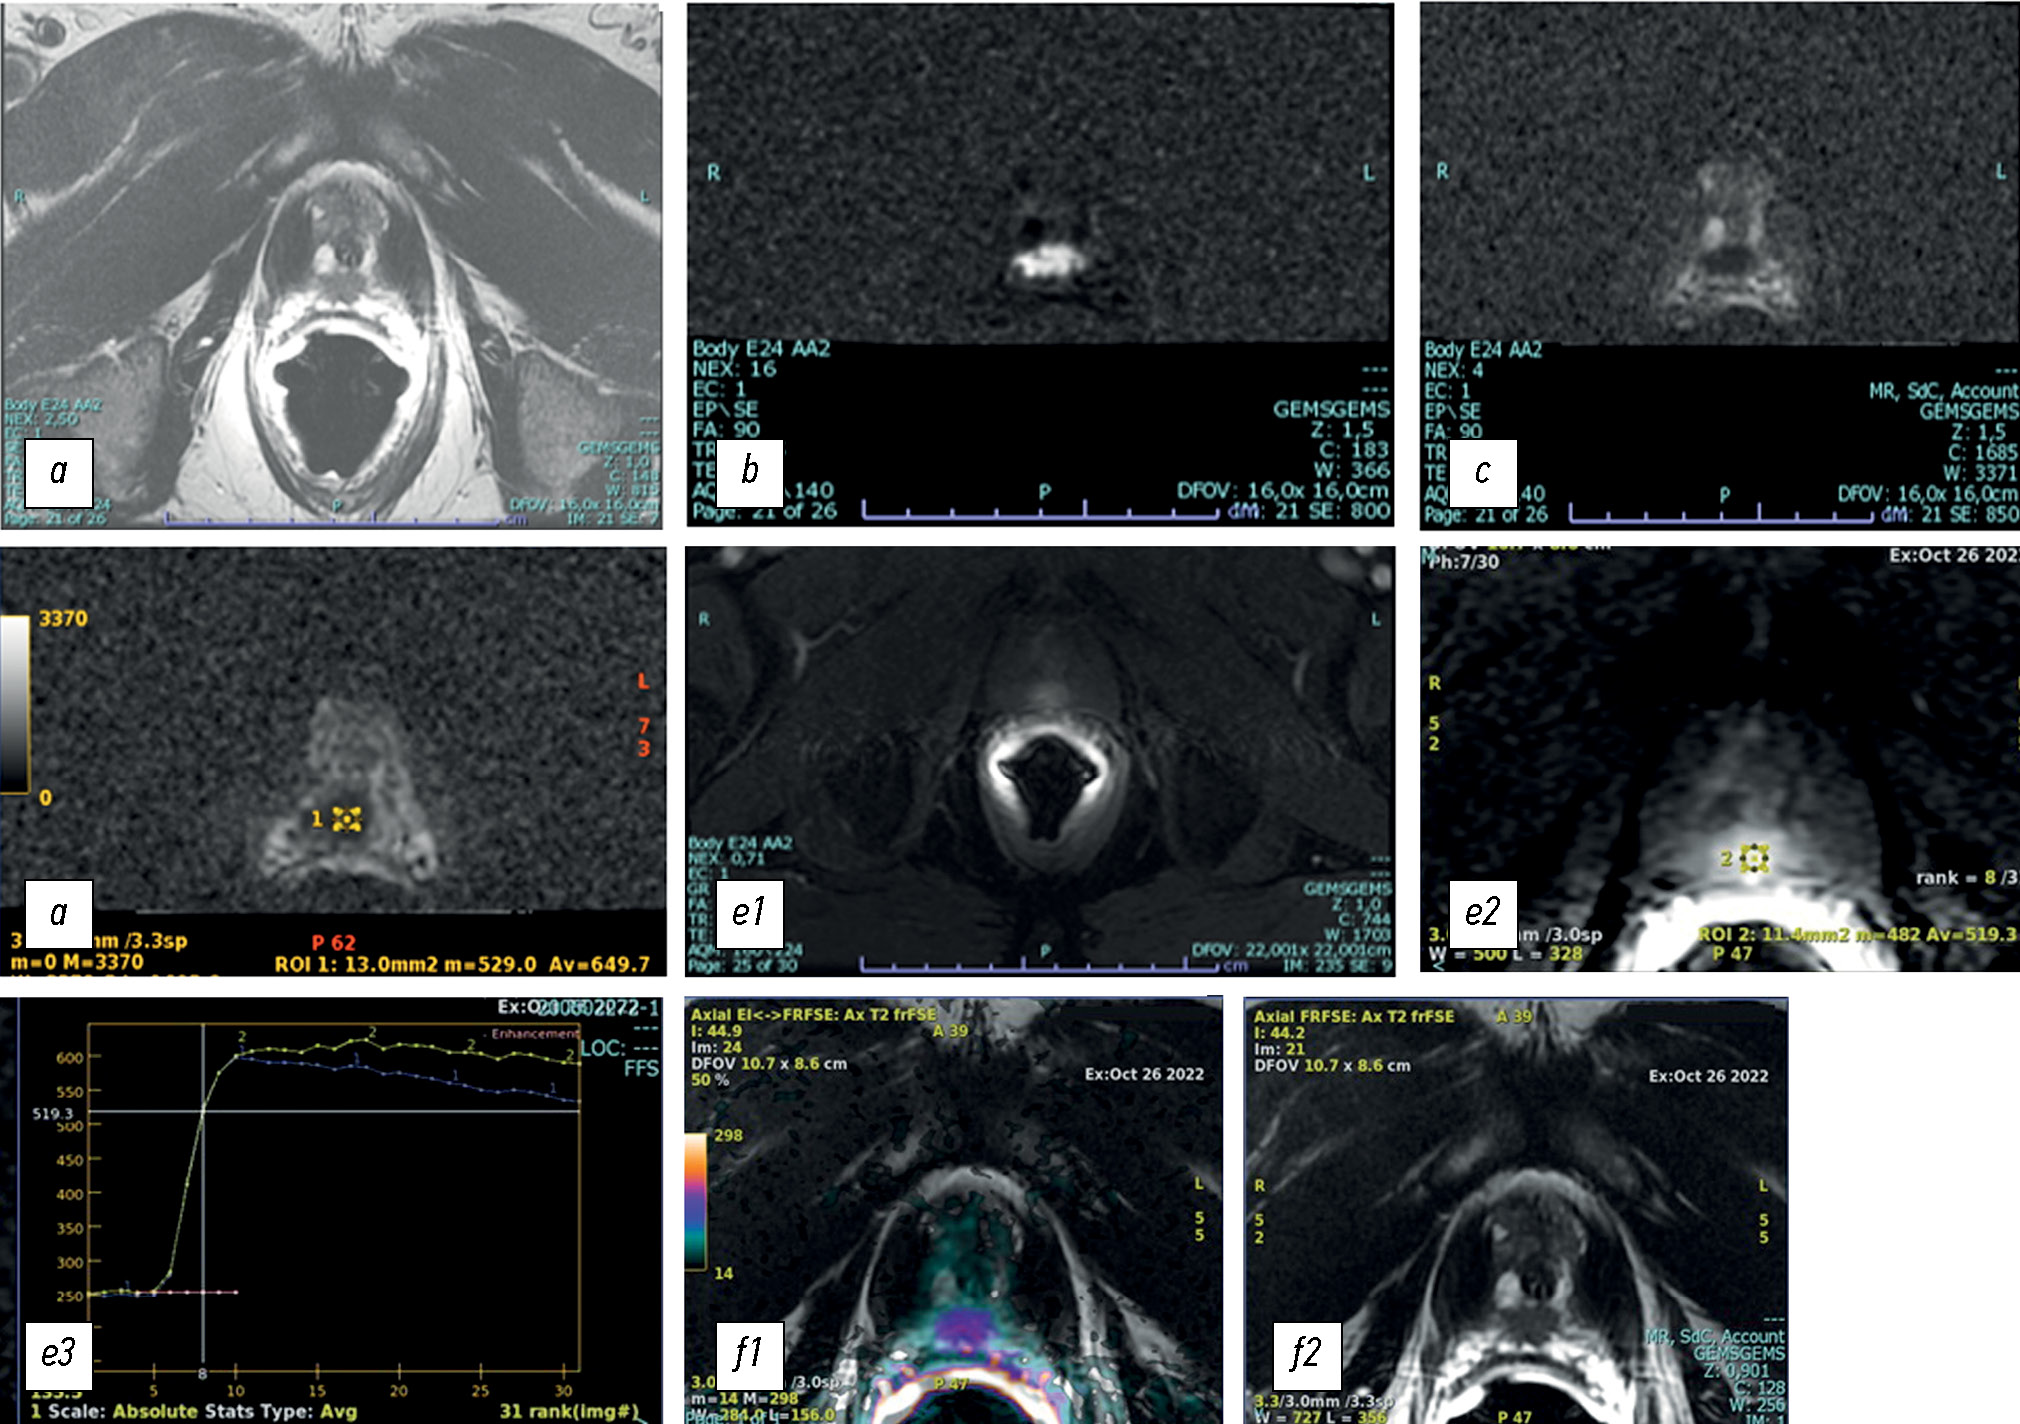

Comparison of the diagnostic accuracy of whole-body diffusion-weighted imaging and 18F-prostate-specific membrane antigen-1007 positron emission tomography combined with computed tomography for detecting bone metastases in prostate cancer

Abstract

BACKGROUND: The increasing availability of 18F-prostate-specific membrane antigen-1007 (18F-PSMA-1007) for prostate cancer staging highlighted its advantages, particularly its higher spatial resolution compared to analogs. Moreover, accumulating scientific data indicate an increase in false-positive findings, predominantly in bones, which may lead to unwarranted upstaging of the disease. Diffusion-weighted imaging may be used for the early detection of bone metastases.

AIM: This study aimed to assess and compare the diagnostic accuracy of whole-body 18F-PSMA-1007 positron emission tomography combined with computed tomography and whole-body and pelvic bone diffusion-weighted imaging in patients with prostate cancer.

METHODS: A retrospective single-center selective study was conducted. The imaging results of 119 patients with prostate cancer were divided into two groups: group 1 comprised 40 pairs of 18F-PSMA-1007 positron emission tomography combined with computed tomography and whole-body diffusion-weighted magnetic resonance imaging scans, and group 2 included 79 pairs of similar studies, with magnetic resonance imaging performed only for the pelvic bones. The diagnostic studies were performed at an inter-study interval ≤14 days. The metastatic bone lesions detected in different anatomical regions was counted using data from 18F-PSMA-1007 positron emission tomography combined with computed tomography and magnetic resonance imaging. Lesions were considered true positives if confirmed by additional magnetic resonance imaging pulse sequences and/or follow-up observation.

RESULTS: Whole-body diffusion-weighted imaging demonstrated higher specificity (58.1%) for detecting bone metastases than 18F-PSMA-1007 positron emission tomography combined with computed tomography (51.06%). However, its sensitivity was lower: 93.22% versus 97.55%.

CONCLUSION: Despite its advantages, 18F-PSMA-1007 positron emission tomography combined with computed tomography shows a high rate of false-positive bone findings. These are most commonly noted in the ribs, vertebrae, and pelvic bones. Suspicious bone lesions should be further evaluated to avoid unjustified disease upstaging. Thus, whole-body magnetic resonance imaging with diffusion-weighted sequences and selective fat signal suppression can be used.